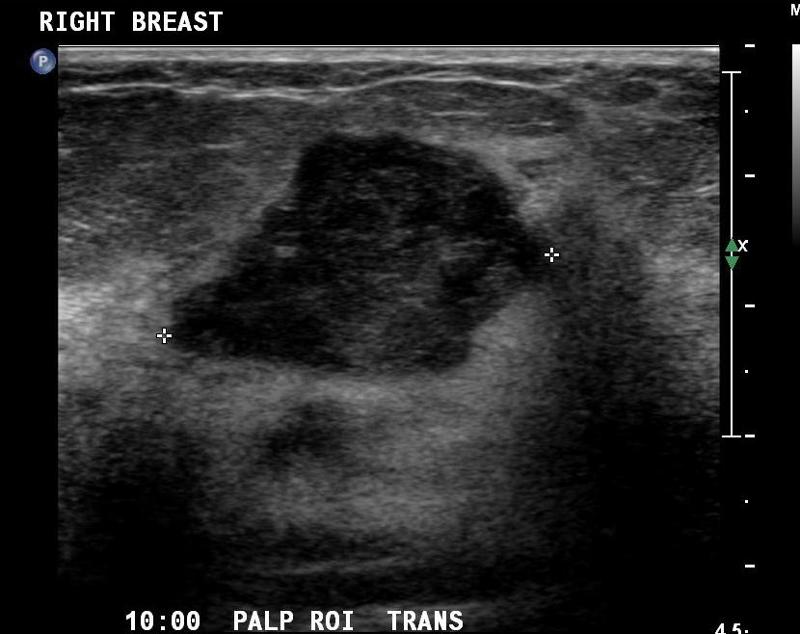

What is the Sonographic Appearance of malignant breast lesions?

Taller than wide

Angular, ill-defined, microlobulations

Thick borders

Echogenic halo

Almost anechoic, heterogenous

Shadowing

Color Doppler - more peripheral and internal flow

Invade tissue planes